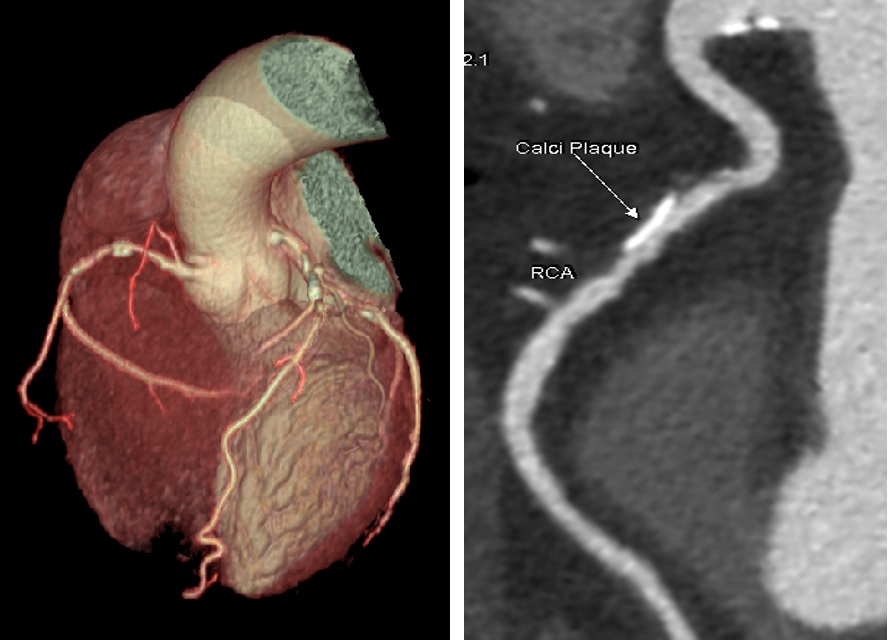

Hình 2. Hình ảnh chụp CLVT 512 dãy đánh giá động mạch vành

- Công nghệ GSI Xtream, công nghệ chụp cắt lớp vi tính phổ theo thể tích đầu tiên với khả năng chuyển đổi mức năng lượng cực nhanh, được thiết kế để tăng cường khả năng phát hiện những tổn thương nhỏ, xác định đặc điểm mô, giảm nhiễu ảnh kim loại. Chụp cắt lớp vi tính phổ được ứng dụng trong việc phát hiện và theo dõi các tổn thương gan, phân biệt các loại sỏi tiết niệu, đánh giá sau đặt coil mạch não, stent graft, các khớp nhân tạo, sau đặt nẹp vít cột sống, đánh giá mức độ phù tủy xương, phát hiện và đánh giá bệnh Gút, chụp tưới máu cơ tim,...